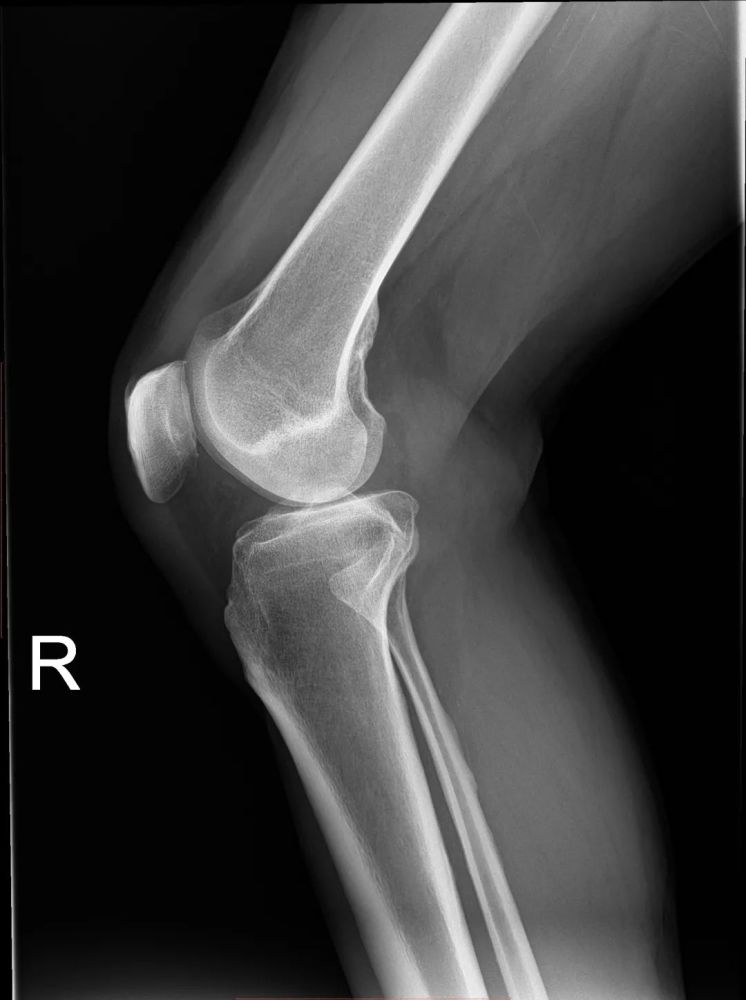

本文图片

一张右腿的X光片 。 X光片其实就是黑白照片 , 而且是负片 。 只不过成像的光源变成了X光 。

有过骨科经历的朋友一定立刻就想到了X光 。 没错 , X光正是不可见光的一种 。 X光片看起来是黑白的 , 是因为X光显影物质只呈现了X光投影的强弱 。